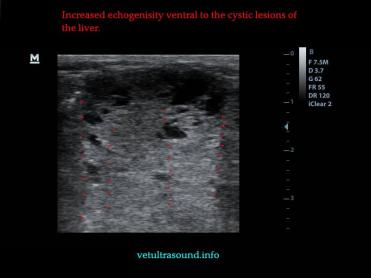

Στον υπέρηχο βρέθηκε ανομοιογένεια του ηπατικού παρεγχύματος, πολυάριθμοι κυστικοί σχηματισμοί οι οποίοι καταλάμβαναν κυρίως τον δεξιό πλάγιο λοβό του οργάνου(pic1&2). Η ροή του αίματος στη πυλαία φλέβα με τη βοήθεια του Pulse Wave Doppler βρέθηκε φυσιολογική(pic3), ενώ σε κλάδο της δεξιάς ηπατικής αρτηρίας ο δείκτης αγγειακής αντίστασης βρέθηκε μειωμένος(normal RI≈ 0.55)(pic4). Στοιχείο που μας δείχνει πως είτε η αγγείωση στη συγκεκριμένη περιοχή είναι νεόπλαστη, είτε λόγω χρόνιας νόσου ο διάμεσος ιστός που περιβάλλει τα αγγεία έχει χάσει την σκληρότητά του. Μικρή ποσότητα ασκιτικού υγρού βρέθηκε ανάμεσα στις εντερικές έλικες. Χωρίς παθολογικά διογκωμένους λεμφαδένες εκτιμήθηκε η κοιλιακή κοιλότητα(pic5). Οι υπόλοιπες δομές ελέγχθηκαν χωρίς παθολογικά ευρήματα.